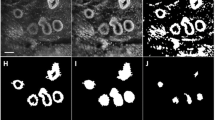

MR images were interpreted by two breast radiologists with more than 10 years of experience and were used to derive the location of the lesions. A region of interest (ROI) was drawn at the lesion site location for all four optical absorption images (e.g., see Fig. 2). For comparison, a similar ROI was drawn at the mirror image lesion site location of the contralateral breast, where no lesion was found. The visibility of the lesions on DOT was assessed both quantitatively and qualitatively. Quantitative values were computed from the volume images of the optical absorption coefficient obtained from the DOT system. The mean absorption coefficient of the ROI was divided by the mean absorption of the background, which included the rest of the breast on that slice except for the lesion (the quantitative score). Qualitative scores for contrast relative to background were given independently by two readers for every ROI, on a scale from −4 to 4, where: 0 = no visibility; 1 = slight heterogeneity seen at the site of the known lesion; 2 = moderate contrast, but less/more than other structures, seen at the site of the known lesion; 3 = contrast at the known lesion site comparable to that of other structures; 4 = major contrast at the known lesion site; a minus sign was used if the signal at the ROI was lower than the background, and a plus sign when it was higher. To learn how to score the images, readers were shown an example set of classified images (not from the study population) before they started the scoring process. All images were made anonymously, placed in random order, and scored by two readers separately, without knowledge from other examinations. Images were scored again after 3 months in a second independent reading by the two investigators.

Examples of ROIs on DOT images compared with MRI. a Patient is a 60-year-old woman with lesion in the right breast; BI-RADS category 2 on MRI (left image T2-weighted MRI with fat suppression); visibility score −4 on DOT (right image); final diagnosis, benign cyst. b Patient is a 56-year-old woman with lesion in the right breast; BI-RADS category 5 on MRI (left image DCE-MRI); visibility score +4 on DOT (right image); final diagnosis, invasive ductal carcinoma